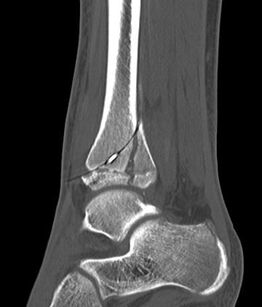

Computertomografie

Die Computertomografie liefert die höchste Auflösung für knöcherne Verletzungen und die Untersuchung dauert nur wenige Sekunden. Nachteilig ist die hohe Strahlenbelastung, die bei einem Vielfachen von konventionellen Röntgenbildern liegt. Bei komplexen Gelenksfrakturen hat die Computertomografie aber auch beim Kind ihre Berechtigung und erleichtert die Planung der Rekonstruktion.

Der teilweise komplexe Frakturverlauf bei Übergangsfrakturen lässt sich im CT zuverlässig darstellen 10. Der erfahrene Untersucher kann bereits mit Röntgenaufnahmen des Sprunggelenks in zwei Ebenen in Verbindung mit zwei 45° Schrägaufnahmen sehr umfassende Aussagen zum Frakturverlauf treffen (v. Laer 2013), die Präzision und Aussagekraft der Computertomografie ist aber zweifelsohne überlegen und wird von den meisten Behandlern bevorzugt 11, auch wenn sich zu diesem Thema in der Literatur eine teilweise sehr emotional geführte Diskussion findet. Einigkeit hinsichtlich der Indikation für ein Schnittbildverfahren besteht bei Triplane-Frakturen, wenn Zweifel darüber bestehen, inwieweit die metaphysäre Fraktur den tragenden Gelenkanteil tangiert 12.